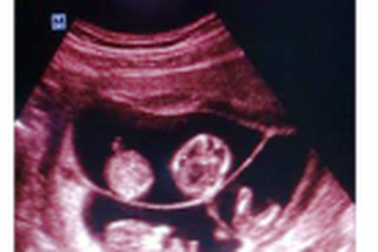

Một phụ nữ mang thai 4 tự nhiên hiếm gặpChiều 19/5, trao đổi với PV Dân trí, ông Nguyễn Đức Cường, Giám đốc Sở Y tế Quảng Bình xác nhận, trên địa bàn tỉnh có phụ nữ mang thai 4 đang được 11 tuần tuổi.

Giám đốc Sở Y tế trực tiếp thăm hỏi thai phụ mang thai 4 tự nhiên hiếm gặpChiều 20/5, ông Nguyễn Đức Cường, Giám đốc Sở Y tế Quảng Bình cùng Phòng Nghiệp vụ Y, Trung tâm chăm sóc sức khoẻ sinh sản đã đến thăm hỏi, động viên sản phụ Hoàng Thị Xuân, đang điều trị tại Khoa Sản phụ, Bệnh viện Hữu nghị Việt Nam - Cu Ba Đồng Hới.